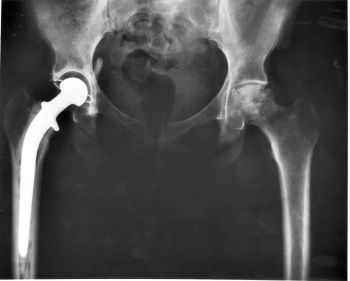

Chirurgia protesica

La moderna chirurgia protesica รจ in grado di offrire impianti diversi con tecniche di impianto sofisticate in modo tale da potere trovare la migliore soluzione per ogni singolo paziente.